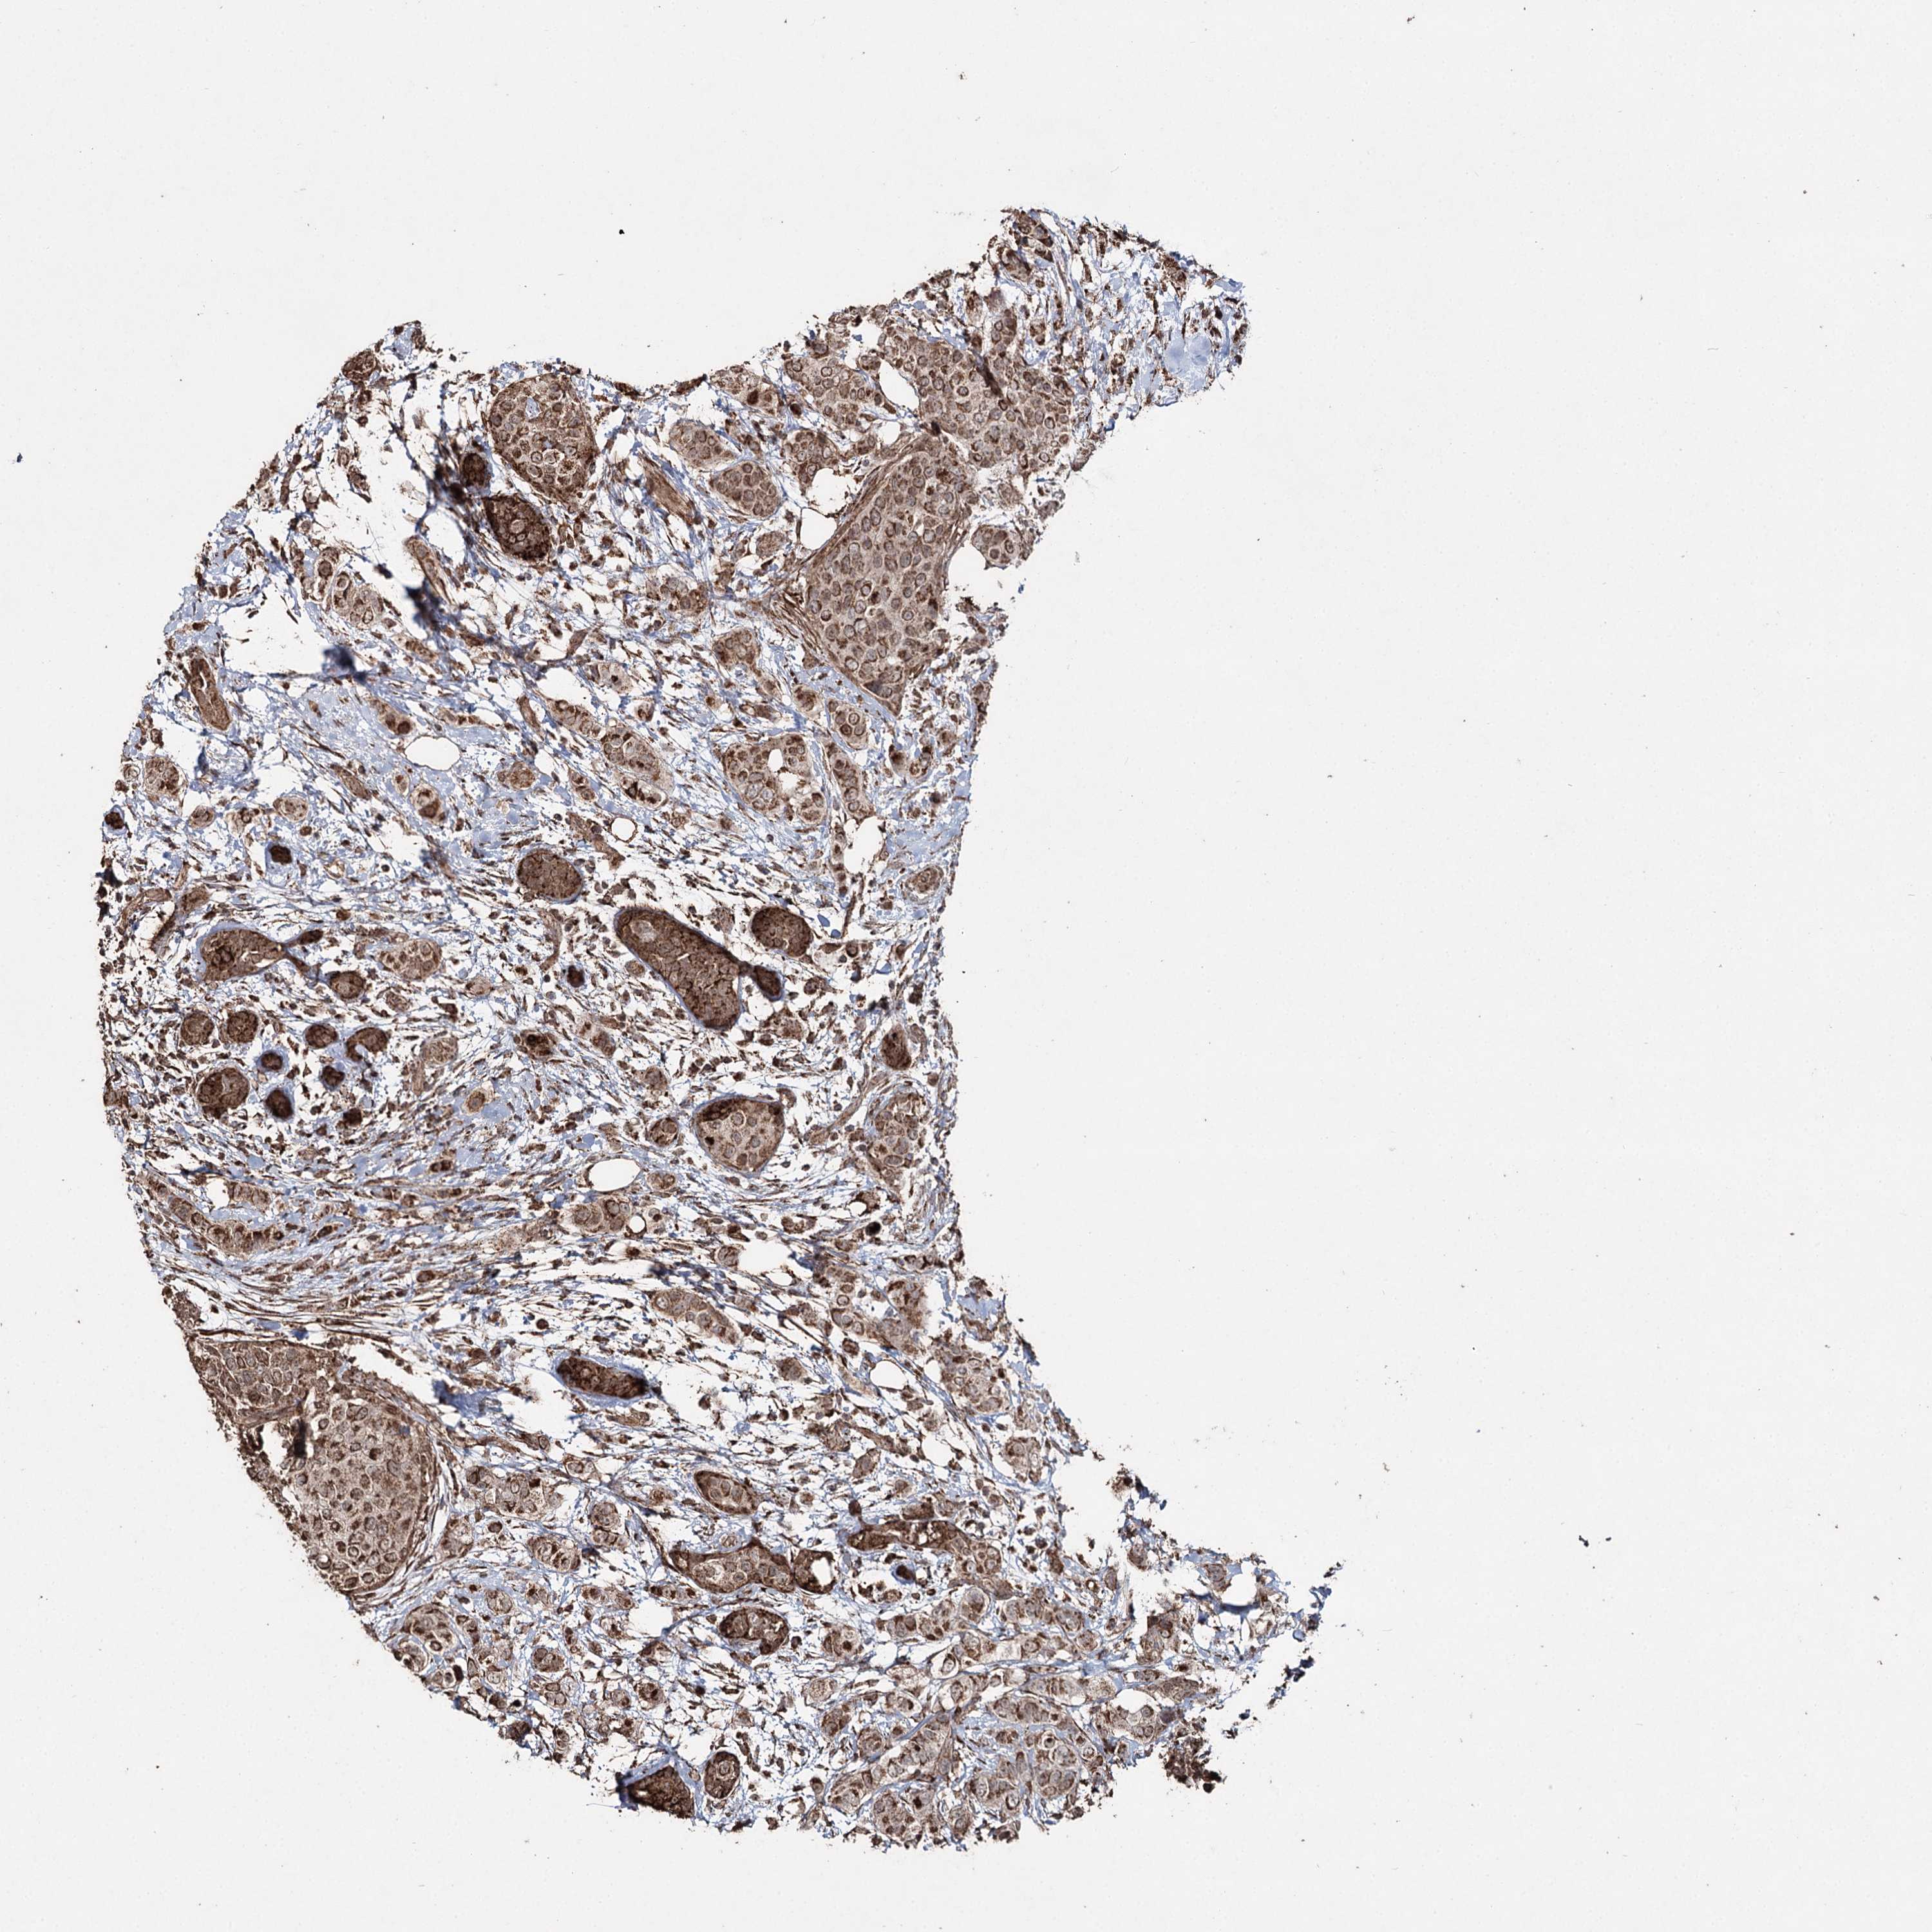

CANCER BREAST CANCER Show tissue menu

BRCA TCGA BRCA VALIDATION PROTEIN EXPRESSION

Breast cancer

Human cancer